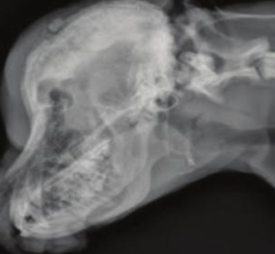

Multilobular osteochondrosarcoma

Slow-growing neoplasia in older dogs that looks like a popcorn ball